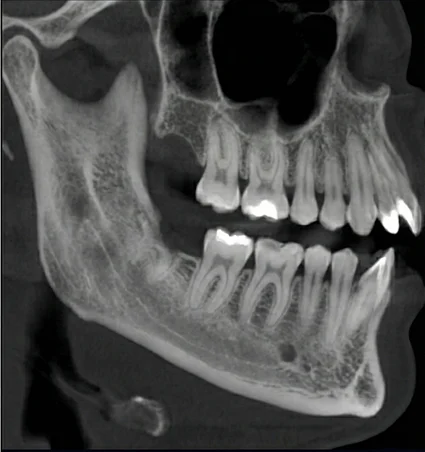

Not every wisdom tooth requires the same type of extraction. Fully erupted wisdom teeth may be removed with a simple extraction using local anesthesia. Teeth that are impacted beneath the gums or bone often require a surgical approach to allow safe removal.

Sedation options such as nitrous oxide, oral sedation, or IV sedation may be used based on comfort needs, with care provided through sedation dentistry when appropriate. Treatment decisions are guided by X-rays, age, oral health, and individual comfort considerations.